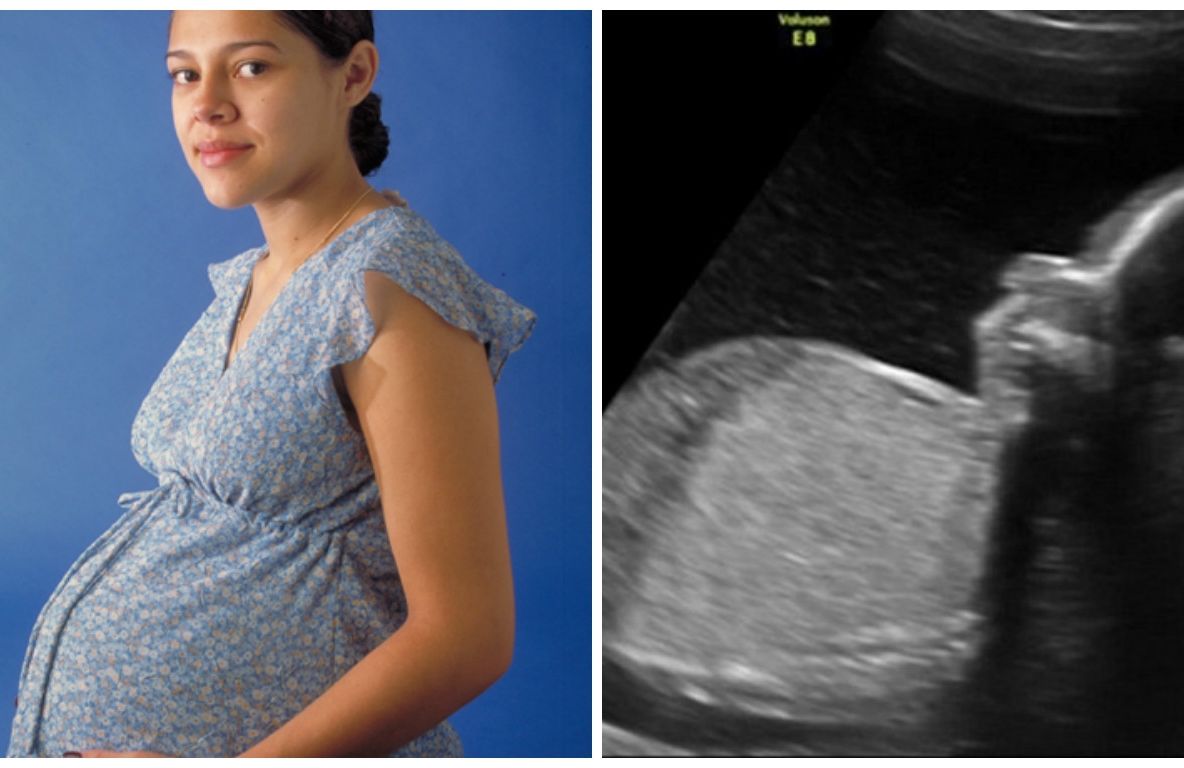

3 nov. 2024, 14:01ActualO durere acută în abdomen s-a dovedit a fi o TUMORĂ DE 30 DE KG. Fenomenul medical care i-a uimit și pe doctori: "Niciodată nu am văzut așa ceva"

1 iun. 2017, 11:24ActualCând a ajuns la spital, medicii au zis că e însărcinată. Fata a negat. Ce i-au găsit în burtă..ȘOC

11 mai 2017, 11:21ActualCând a ajuns la spital, medicii au zis că e însărcinată. Fata a negat. Ce i-au găsit în burtă..ȘOC

3 mai 2017, 13:18ActualA fost în culmea fericirii când a aflat că e însărcinată. Mai târziu a aflat ce creştea în ea. Şoc!

24 mar. 2017, 10:14ActualÎntâi a aflat că e însărcinată, apoi a primit vestea: "Va muri!". Decizia femeii a fost clară

28 sept. 2016, 19:51ExternO gravidă credea că vorbeşte cu Isus! Când a născut medicii au înlemnit. Ce se ascundea în burta ei

27 sept. 2016, 21:45ExternA crezut că este însărcinată, dar când a ajuns la medic a suferit un şoc! Ce avea în burtă?